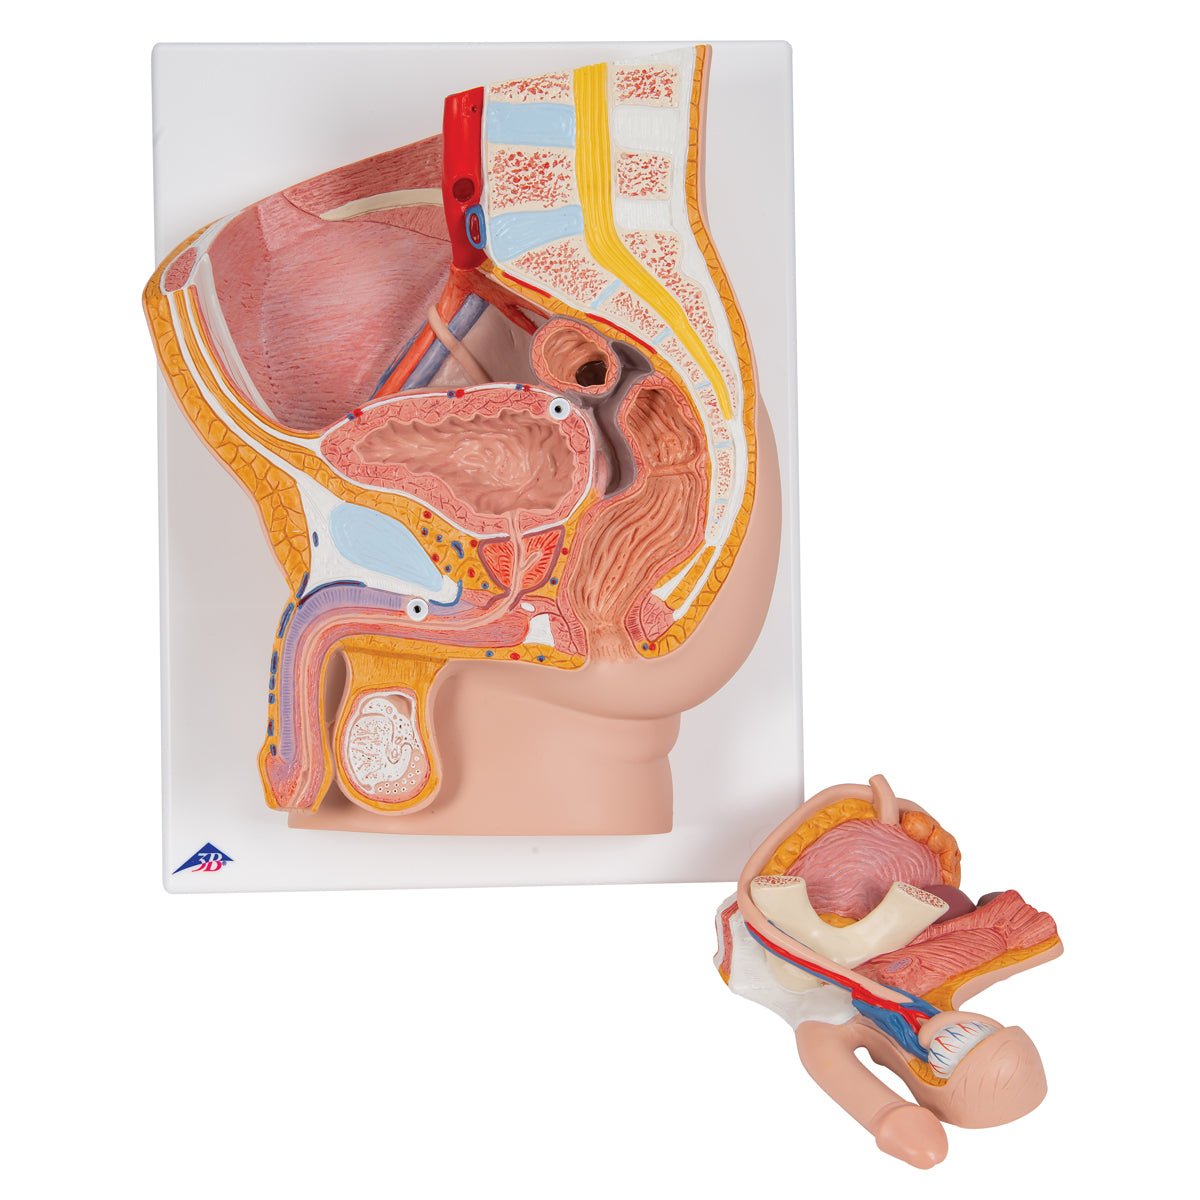

Salg af anatomiske modeller er det bærende element i eAnatomi, selvom vi også bruger mange ressourcer på at udvikle vores egne anatomiske materialer som fx plakater. Anatomiske modeller anvendes til forskellige formål og kan både vise afgrænset væv, organer samt organsystemer. Søger du en simpel model af knoglevæv eller måske en avanceret torso-model baseret på MRI teknologi, kan du finde det hele på eanatomi.com.